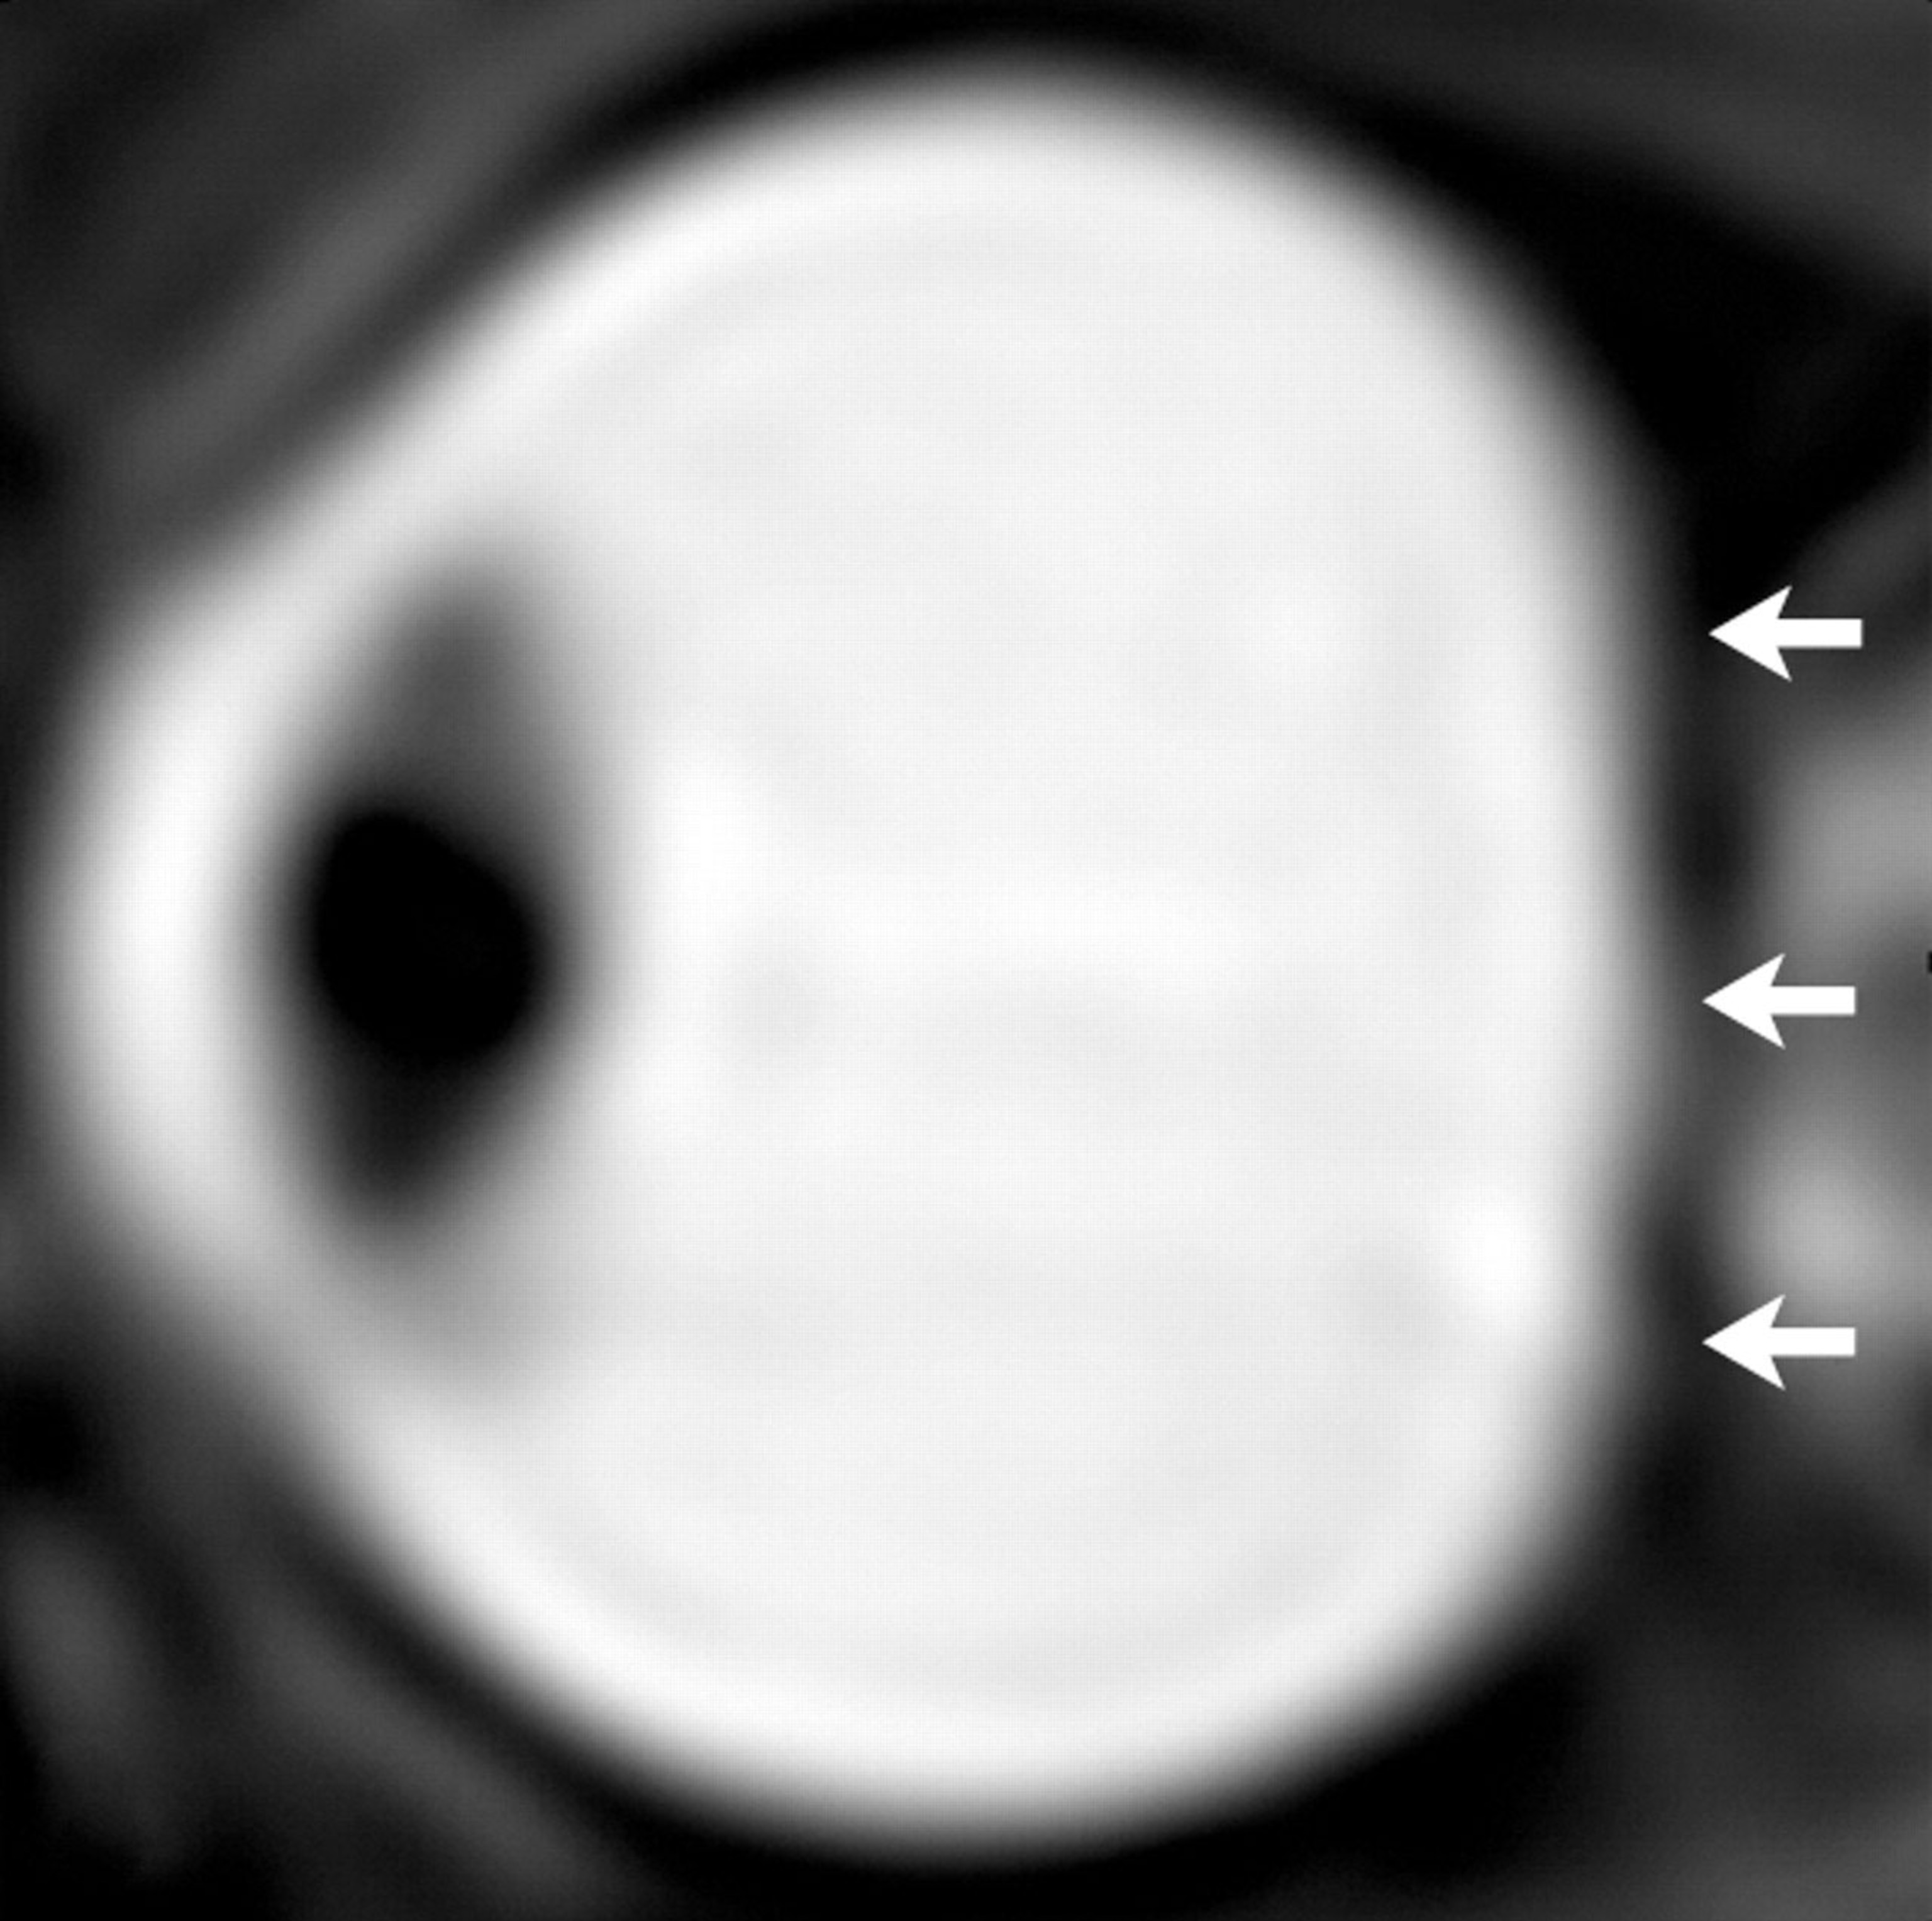

Alperin and his colleagues reached this conclusion by conducting high-resolution MRI scans on seven astronauts before and shortly after long-duration missions. They then compared those results with scans of nine astronauts who had flown on short space shuttle missions.

The researchers found that the seven astronauts who had spent months in orbit had considerably higher volumes of CSF within the skull cavities that hold the eyes. This increased the pressure on the back of the astronaut’s eyeballs, causing them to flatten and leading to increased protrusion of the optic nerve.